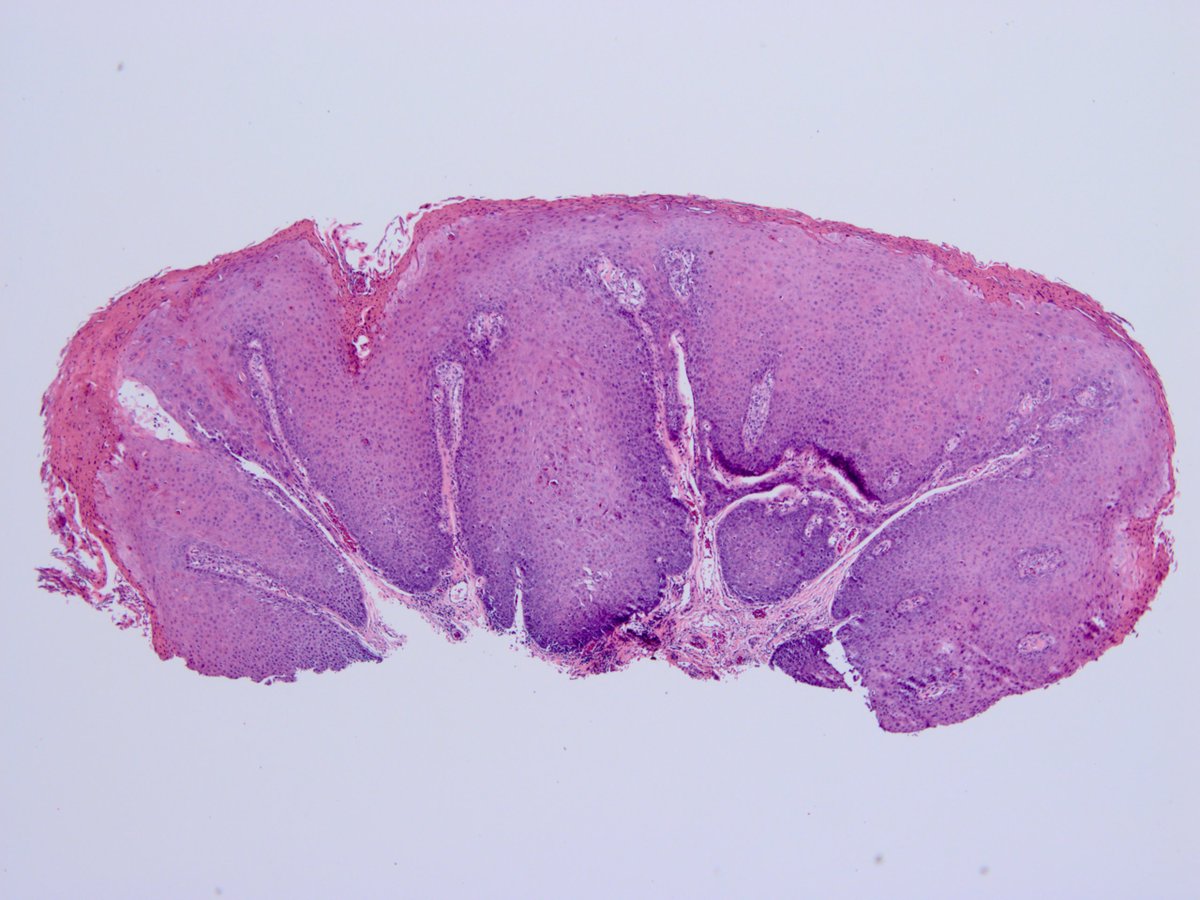

HPV-associated CIS/bluntly inv scca in tongue of 83 year old female with apoptotic and karyorrhectic cells https://t.co/rWKHypuxFw